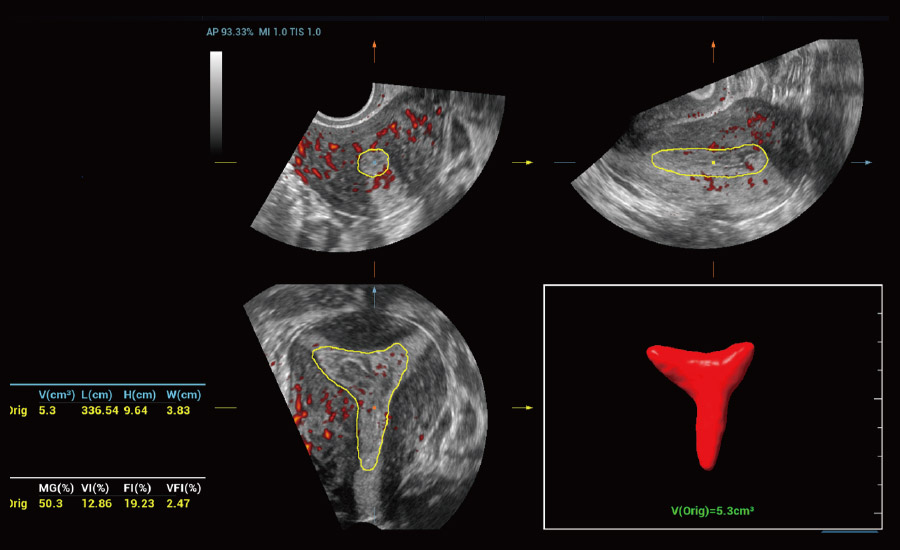

UMA (Ultra-Micro Angiography)

The innovative technology breaks the bottlenecks of traditional Doppler imaging. With ultra-high spatial resolution and flow sensitivity, it allows detecting super-subtle and super-slow flow perfusions, thereby extending the clinical application of qualitative and quantitative ultrasound evaluation in fetal brain, kidney, placenta, endometrium, ovary, etc.

UMA - uterine and endometrial flow